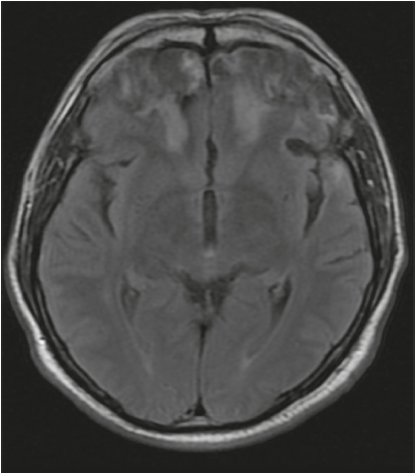

El cribado cognitivo mostró un Mini-Mental de 29/30, con un error en evocación diferida; no se apreciaron intrusiones significativas, pero sí dificultades para la abstracción. La aparente preservación de las funciones ejecutivas motivó un examen a mayor profundidad con el test de MoCA, que puntuó 23/30, a expensas de evocación diferida, fluidez verbal y abstracción, y se evidenciaban fallas en memoria de trabajo. Debido a la afección prefrontal clínica, se aplicó la Frontal Assesstment Battery (FAB), una escala de cribado de fácil aplicación utilizada para valorar funciones prefrontales28, que puntuó 12/18, a expensas de abstracción, fluidez verbal, programación y control inhibitorio. La resonancia cerebral mostró áreas de encefalomalacia en polos frontales bilaterales, BA 10, y córtex orbitofrontal, BA 11, de predominio derecho, con zonas hiperintensas de gliosis en sustancia blanca adyacente bilateral, además de una zona de contusión en el polo frontal derecho, BA 38, como suele ocurrir en traumatismos craneoencefálicos por aceleración-desaceleración (figura 1).